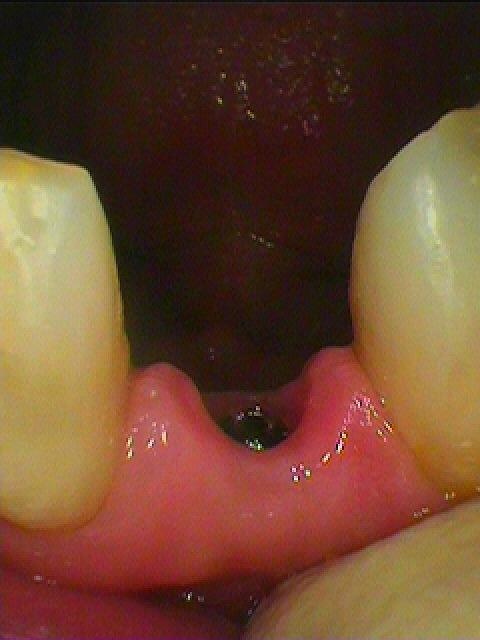

仮歯の状態

仮歯を外していきました

3か月たち傷も癒えてきました

歯肉の形態を付与していきました

このふくらみがフレアーでないので技工士にできないかの打診を図りフレアーにしていきます